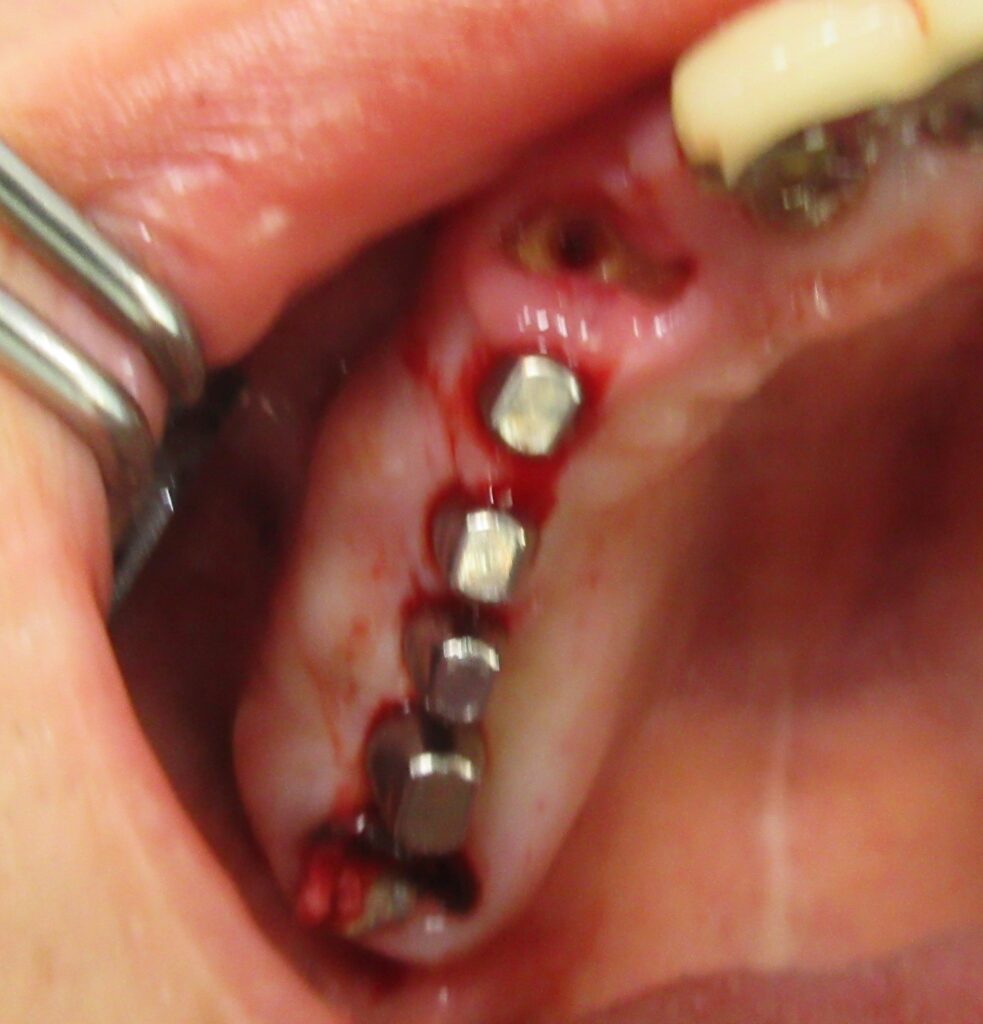

麻酔が効いている事が確認されると、すぐにオペ開始です。

まずは右上4番目の歯茎から骨の部分までを穴開けパンチの要領で穴を開けていきます。

くりぬいた部分の歯肉を取り除き、次は骨に穴を開けていきます。

ドリルの先端を細い物から徐々に大きい物に変えながら、植立するインプラント体のネジの部分を除いた胴の部分の太さに合わせた大きさの穴を開けていきます。

開けた穴に、専用道具を使ってネジを締めるように長さ2センチ程のインプラントを骨に埋め込んでいきます。

続けて他の歯も同じように植立していきます。

インプラントオペでは、複数本を植立する場合でも、当時進行はせず、1本ずつ同じ工程を繰り返して植立します。